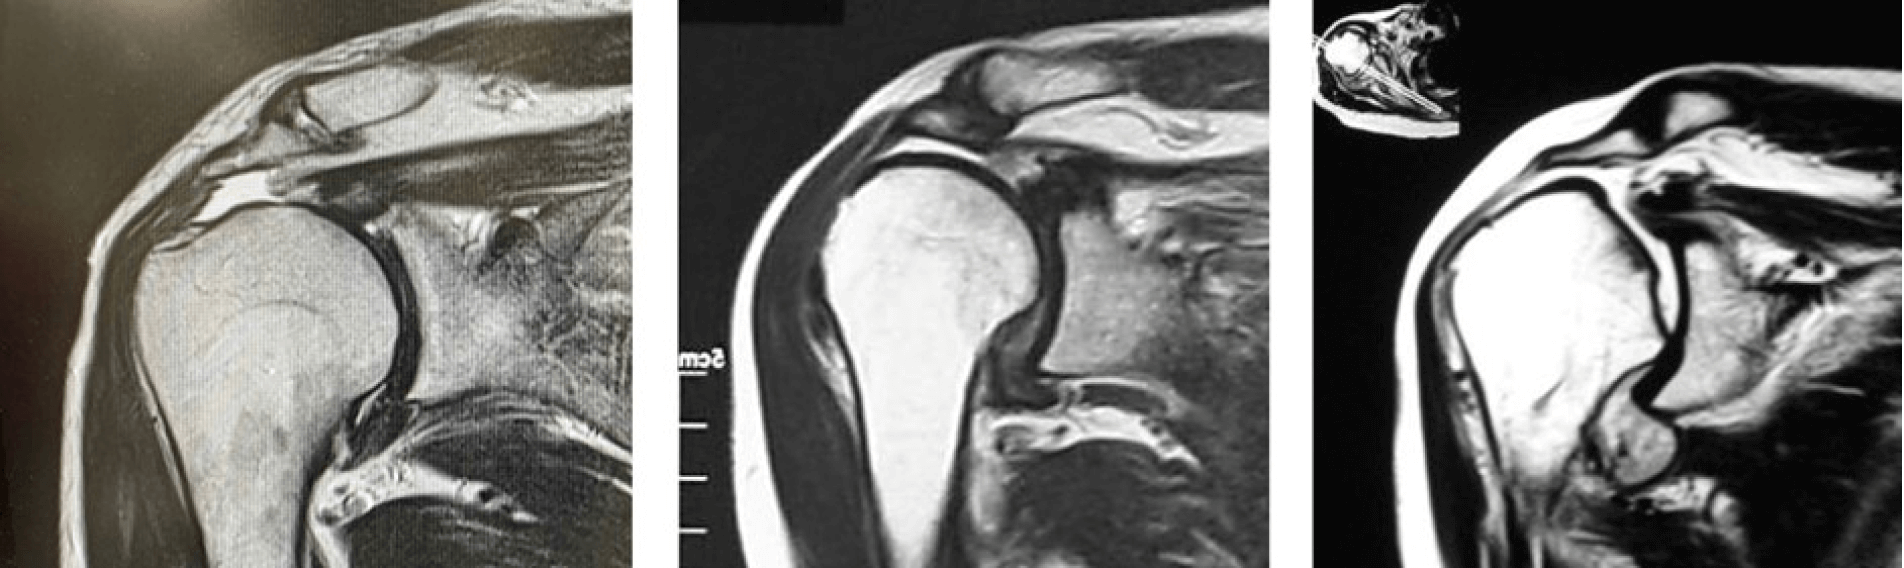

腱板断裂のMRI画像

左 腱板修復が可能

中 自家大腿筋膜移植術が必要

右 人工肩関節置換術が必要

肩腱板断裂に対する手術の選択肢は幅広く、断裂が大きくなりますと“自家大腿筋膜移植術”や“人工肩関節置換術”が必要になることもありますが、筋膜の移植や人工関節に抵抗を感じる方も多いでしょう。肩の痛みを放置し断裂が拡大しますと、このような大がかりな手術が必要となる可能性があります。自分の腱板のみで修復できる段階で治療に臨めるよう、少しでも気になる症状があれば早めにご相談ください。